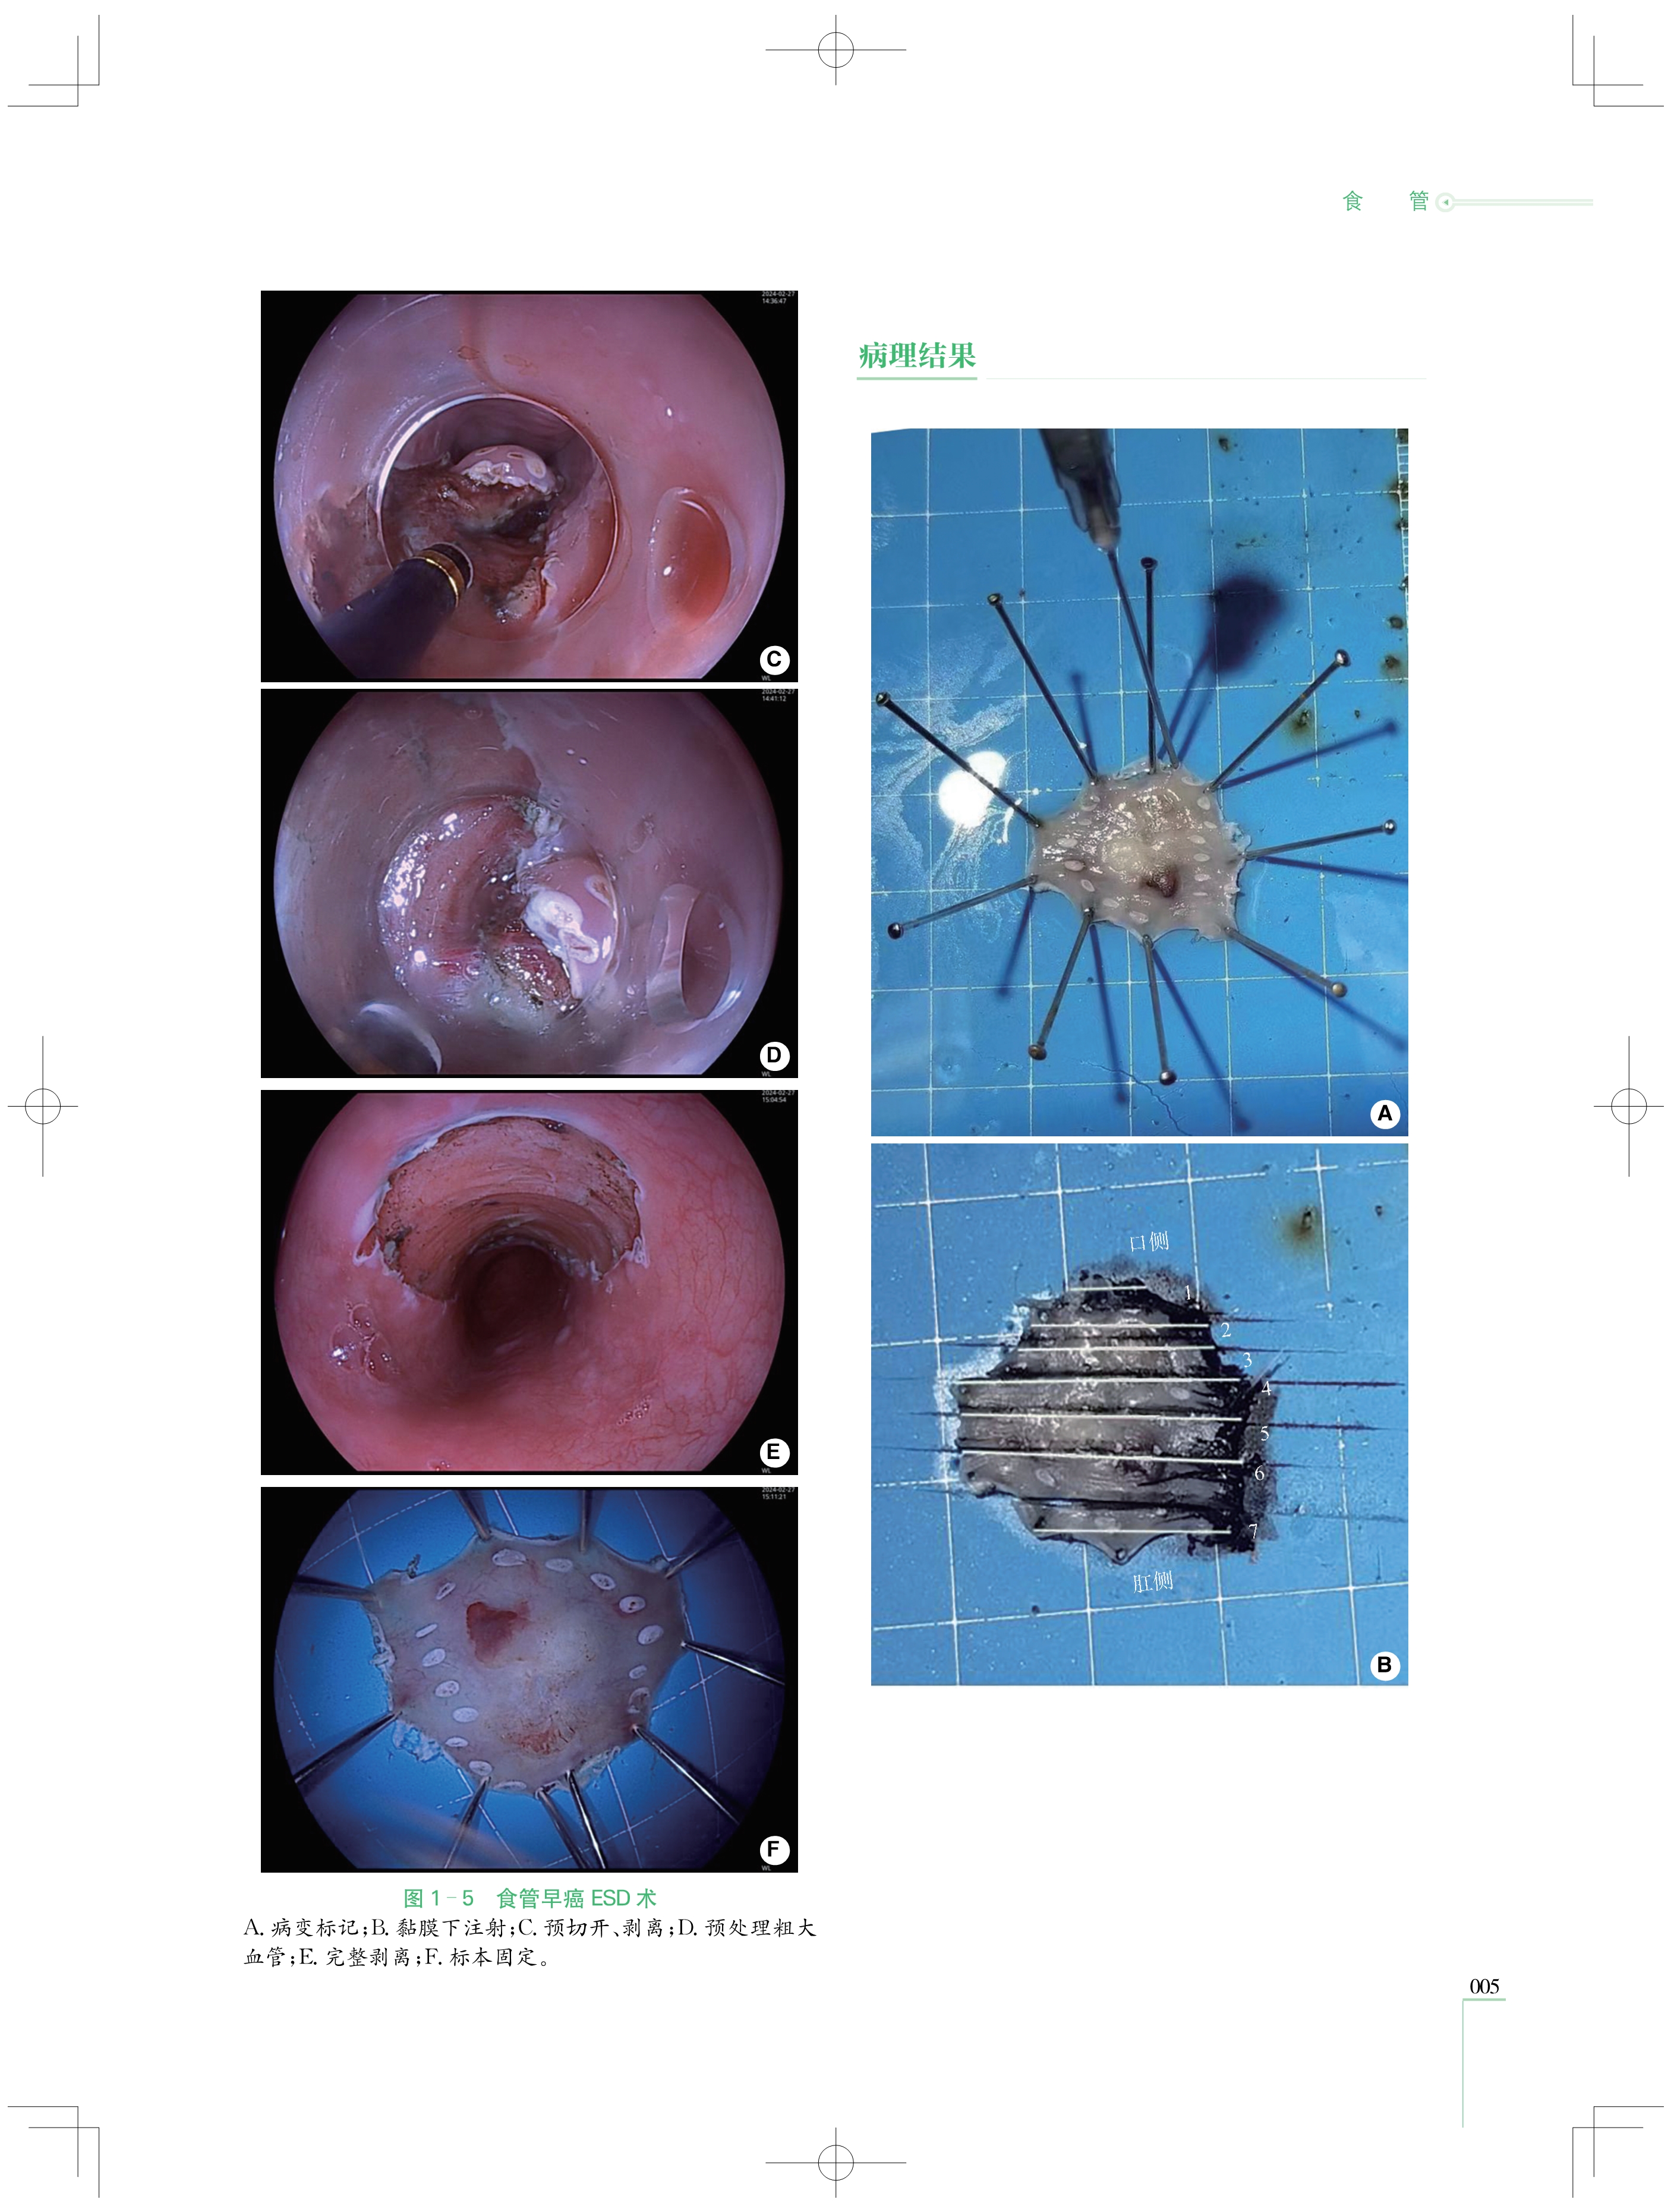

本书收集了第一届至第五届“ 中国介入性EUS视频大赛 ”的优秀获奖病例共计87例,涵盖超声微探 头及介入性超声内镜( EUS)两大领域,这些病例皆历经严格筛选,具有极高的代表性和典型性,全面覆盖了 消化系统的复杂疑难病症。从极为罕见的消化道黏膜下病变,到极易混淆的纵隔占位性疾病,每一个病例 都翔实还原了诊疗经过、超声图像与病理对照,为读者展现完整且严谨的诊断思维体系,帮助读者在复杂的 病情中抽丝剥茧,精准把握疾病本质。